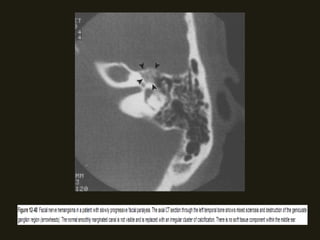

SCHANOMAS DOS NERVOS FACIAIS

• Mais comuns no gânglio geniculado, labirinto e segmentos timpânicos;

• Sintomas – diminuição da acuidade auditiva, paralisia facial...

• RM – lesão isointensa T1 e iso/hiperintensa em T2;

• TC – erosões ósseas da porção antero-superior do CAI e do gânglio

geniculado são sugestivas;

• Pode disseminação extracanicular – massa tumoral localizada além do

canal do nervo facial, na área supralabiríntica, orelha média, mastóide,

parótida;